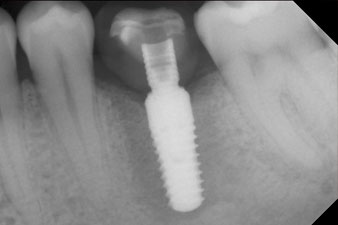

The implant was uncovered two months later and a gingiva former was screwed in (no picture).

After healing of the soft tissue, the implant stability was measured again before delivery of the prosthetic restoration.

Both values were virtually unchanged and were between the medium and the high range – where the lower value is always used as the reference value that determines the treatment.

Therefore, successful osseointegration and adequate biological stability could be recorded, which enabled an impression to be taken in the same session.